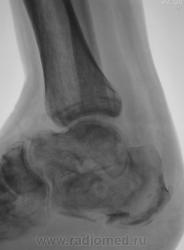

Лечение состояло из "множества рентгенов" и гипса. Срок - 5 месяцев.

Сейчас думают об остеомиелите.

Контуры пяточной кости относительно четкие, разрежение структуры пяточного бугра, в проекции перелома уплотнение структуры кости( имею в виду последние снимки).Клиника остеомиелита есть?

Во-первых, деформация пяточной кости; во-вторых, отсутствие консолидации, через некоторое время и ложный сустав сформируется. Неоднородное уплотнение костной структуры в теле кости может быть обусловдено как остеомиелитом, так и перераспределением нагрузки.

Признаков остеомиелита не вижу, только консолидир перелом с неуд стоянием отломков.